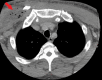

Figure 2

Figure 2. Computed tomography of the chest axial view reveals soft tissue swelling involving the right pectoralis muscle group extending into the anterior mediastinum, suggestive of a developing abscess with mediastinitis (red arrow).